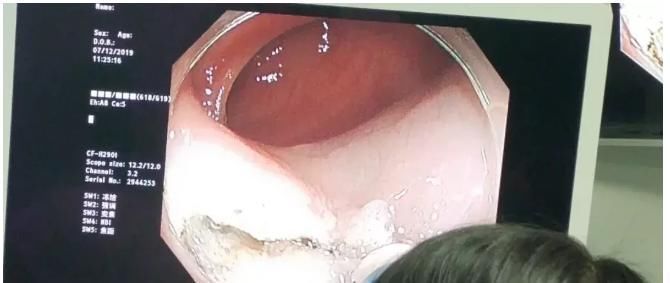

今年56岁的王阿姨前几天体检做了个胃镜精查,医生取了活检送病理,今天结果出来了:萎缩性胃炎,胃窦局灶符合低级别上皮内瘤变。

胃粘膜低级别上皮内一般是胃镜下活检病理诊断的,与胃癌的发生关系密切。

但不是所有的低级别上皮内瘤变都会变成癌,具体要结合胃镜观察来判断。

因此,如果病理活检诊断为低级别上皮内瘤变,首要的是需要进行放大染色内镜(精查胃镜)检查,才能评估该低级别上皮内瘤变是否有问题,是选择手术、内镜下治疗、药物治疗还是只需要随访。